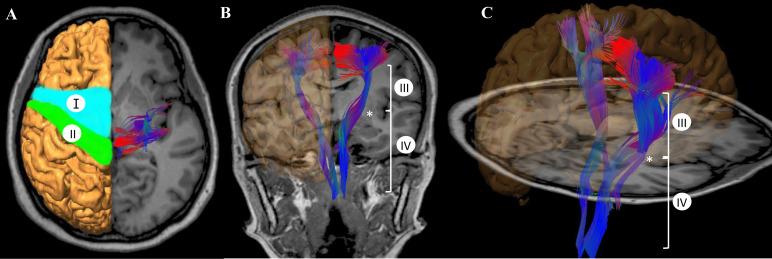

A total of 125 patients who underwent microsurgical resection of M-AVMs were retrospectively reviewed. Four subtypes were identified based on nidus location: (I) nidus involving the premotor area and/or supplementary motor areas; (II) nidus involving the precentral gyrus; (III) nidus involving the corticospinal tract (CST) and superior to the posterior limb of the internal capsule; (IV) nidus involving the CST at or inferior to the level of posterior limb of the internal capsule. In addition, we divided type IV into type IVa and type IVb according to the AChA feeding. Surgical-related motor deficit (MD) evaluations were performed 1 week (short-term) and 6 months (long-term) after surgery.

回顾性分析了 125 例接受显微手术切除的 M-AVM 患者。根据病灶位置确定了 4 个亚型:(I)病灶累及运动前区和/或辅助运动区;(II)病灶累及中央前回;(III)病灶累及皮质脊髓束(CST)并位于内囊后肢上方;(IV)病灶累及 CST 并位于内囊后肢水平或下方。此外,我们根据 AChA 供血将 IV 型分为 IVa 型和 IVb 型。术后 1 周(短期)和 6 个月(长期)进行与手术相关的运动障碍(MD)评估。